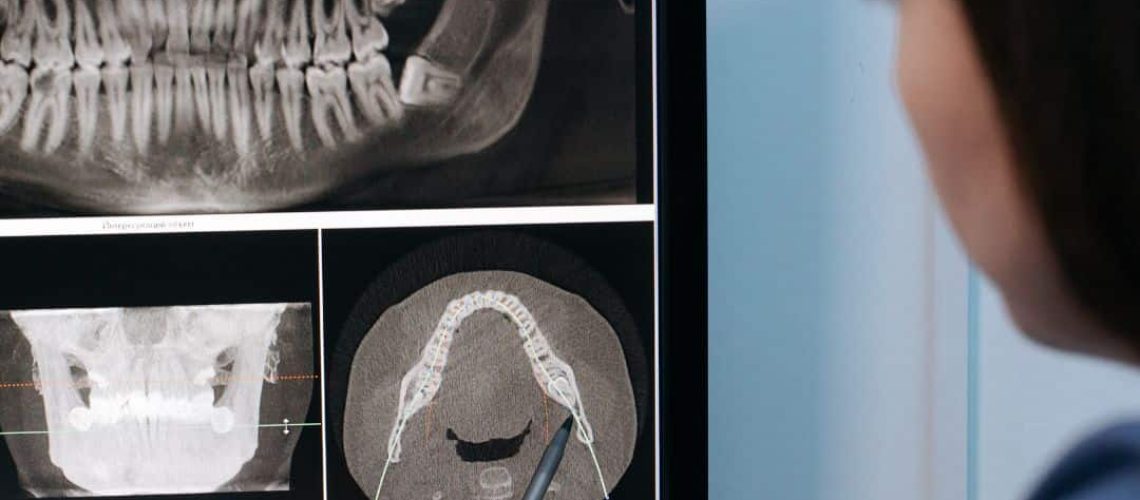

- Radiographies intra-orales

- Radiographies panoramiques (avec ou sans céphalométrique)

- Scanner CBCT (avec ou sans panoramique/céphalo)